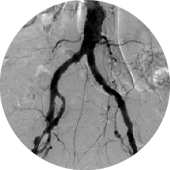

<手術前>両側総腸骨動脈(お腹の中にある足のつけねの動脈)と両側大腿動脈(太ももの動脈)に閉塞、狭窄部位があり、運動障害(間歇性跛行)や皮膚障害(壊死)を引き起こし、車椅子に乗られての入院となりました。

<手術後>右の鎖骨下~腋窩動脈(鎖骨の下から脇の下にかけての動脈)から両側大腿動脈、さらにそこから両側膝窩動脈(膝の裏の動脈)にバイパス手術を施行しました。

運動障害、皮膚障害も改善し、歩いて退院されました。

右鎖骨下〜膝窩動脈吻合

両側総腸骨動脈吻合部

両側大腿動脈吻合部